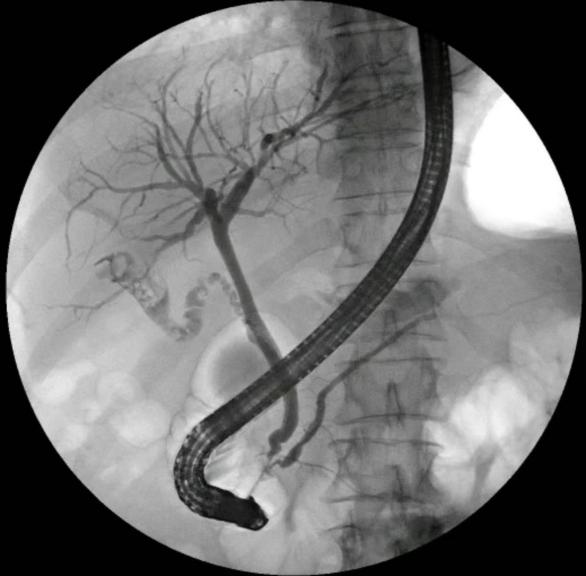

传统开腹手术创伤大、恢复慢,对刚经历生产的张女士来说,无疑是二次伤害。医疗团队决定为张女士进行ERCP(经内镜逆行胰胆管造影)手术,这是一种“零切口”微创技术。

术中,医生将内镜从口腔送入,直达“事故现场”,精准切开乳头、取出6mm结石、清理胆道、放置引流。手术全程没有刀口、没有出血,更无辐射风险,仅用20分钟,“炸弹”顺利拆除。